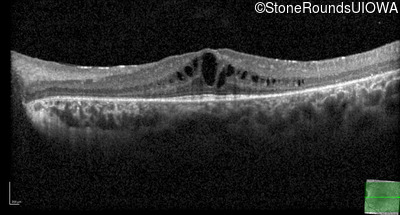

Age at visit: 7 years

OD OS

Age at visit: 9 years